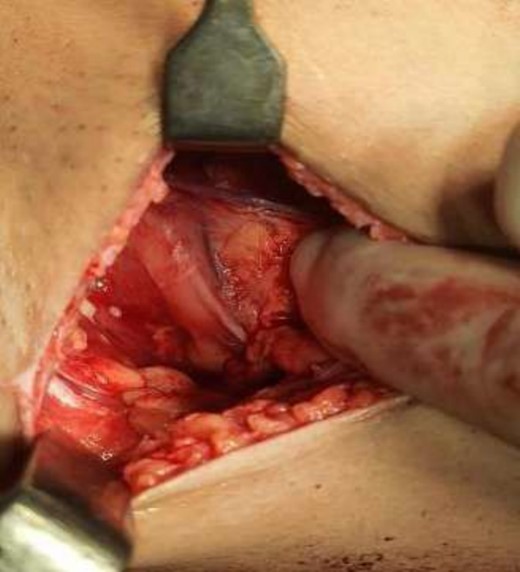

The operating surgeon opted for a vertical mastopexy to remove the mass and simultaneously reconstruct the breast to restore it as much as possible and to have a cosmetically better scar (Fig. 7). The skin was marked, a peri-areolar ellipse having a diameter of about 15 cm was made that extended vertically below, 4 cm above the inframammary fold. The skin was dissected along the incision line and the mass was removed. Grossly, the specimen measuring 5 × 3.5 × 3 cm3, containing the firm mass, was sent for histopathological analysis. Axillary lymph node biopsy was done. Two drains were placed, and the skin was closed in the form of a superior circle and an inferior ellipse (Figs 3–6).

Mastectomy along with sentinel lymph node biopsy procedure (Sentinel Lymph node Biopsy).

The frozen section diagnosis revealed secretory carcinoma, unifocal, 2.3 × 1.7 × 1.5 cm3 in size. Skin was unremarkable and free of tumor. There was no intraductal component. All the resection margins were free of tumor and the closest superior margin was free by less than 0.1 cm. A total of 16 lymph nodes were isolated from axillary tissue, all of which were negative for metastatic carcinoma (0/16). No venous, lymphatic or perineural invasion was identified. Pathological staging revealed primary tumor; pT2, lymph nodes; pN0, distant metastasis; pMx. Estrogen and progesterone receptors were negative (Fig. 8).

Mastectomy along with sentinel lymph node biopsy procedure (Tumor extracted).